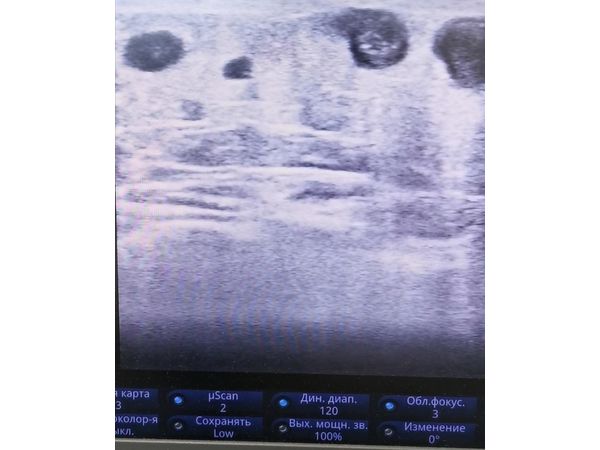

УЗИ левой голени показало:

- тромбы (гиперэхогенные включения) в расширенных притоках большой подкожной вены (БПВ), которые закупоривают их просвет и не дают крови нормально циркулировать;

- калапанную недостаточность СФС (в месте впадения большой подкожной вены в глубокую бедренную вену), которая сопровождается обратным током крови (рефлюксом);

- горизонтальный рефлюкс на фоне клапанной недостаточности перфорантных вен нижней трети голени.